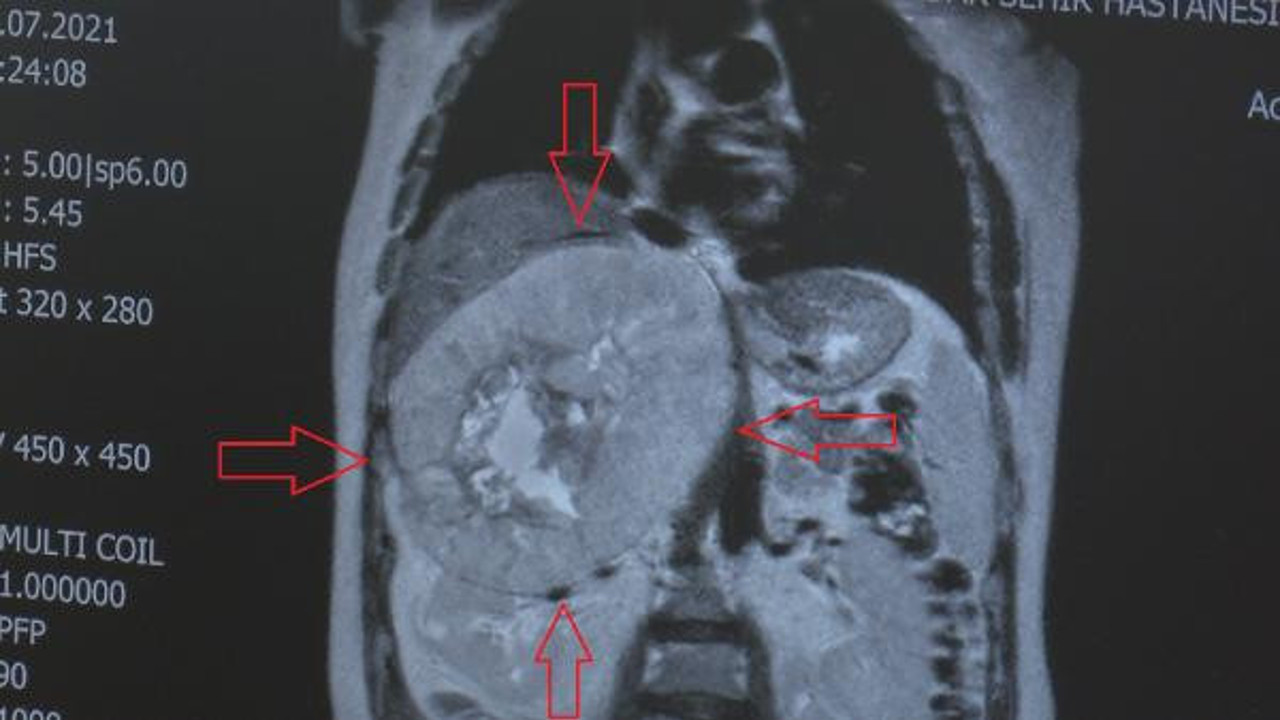

Operasyonu gerçekleştiren ekibin başında yer alan Doç. Dr. Akça, "Hastamız bize başvurduğu zaman kitlesel tanısı zaten konmuştu. Sağ tarafında, ilk önce ayırt edilemeyen böbrek kaynaklı mı, yoksa böbrek üstü bezi kaynaklı mı olduğu bilinmeyen dev bir kitle vardı. Çapı yaklaşık 30 santim boyutlarında, bir basket topu büyüklüğünde bir kitleydi. Böbrek üstü bezi tümörü olduğunu gördük ve ameliyata karar verdik. Kitle, tomografide gözüktüğünden çok daha büyüktü. 7,5 kilo civarında bir kitle çıkardık. Böbreğe, karaciğere, vücudun ana toplardamarına, atardamarına, hatta vücudun orta hattını geçecek şekilde büyük bir kitleydi" dedi.

Böbrek üstü bezi tümörlerinin normalde daha küçükken belirti verdiğini ve saptanabildiğini anlatan Doç. Dr. Akça, "Genellikle insidental, yani rastlantısal şekilde saptanır. Hasta bir şekilde başka bir şikayetle gelir ve teşhis konur. Ama bu kadar büyük olanına literatürde de çok az rastlıyoruz. Çünkü hasta bir şekilde hissediyor. Bu hastada bir denge problemi yapacak kadar büyük bir kitle vardı. Hastamız bize geldiğinde 106 kilo civarındaydı. Ameliyattan sonra 95 kiloya düştü. Şu anda da normal hayatına dönmüş durumda. Bütün damarlara, karaciğere falan yapışık olan kitlelerde tedavi bir ekip işidir. Evet üroonkoloji açısından ekibin başında ben varım ama ameliyatı ve diğer tedavilerini diğer hocalarımızla beraber yapar ve planlarız. Bu ameliyatta da genel cerrahi ve radyasyon onkolojisi ile birlikte hareket ettik. Zaten tedavi sadece ameliyatla bitmiyor. Hastamıza radyoterapi de vereceğiz. Çünkü ''adenokortikal karsinom'' (böbrek üstü bezi tümörü), nüksetme ihtimali olan bir tümör" diye konuştu.